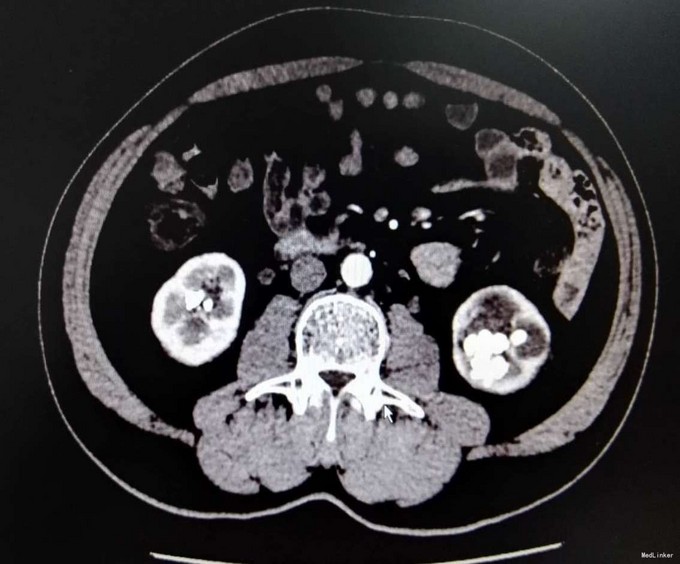

3、查体:未见明显阳性体征 4、辅助检查:外院平片:双肾多发结石;我院CTU:双肾多发结石,左侧肾盂输尿管连接处结石,并双肾积水,左肾明显,双侧肾盂、输尿管炎症。

5、诊断:肾结石(双肾多发结石) 6、治疗:入院后完善相关检查,双肾CTU:双肾多发结石,左侧肾盂输尿管连接处结石,并双肾积水,左肾明显,双侧肾盂、输尿管炎症。排除手术禁忌症后行左侧PCNL术,术后恢复良好,拔出肾造瘘管后,先出院休息,2周后返院进一步治疗